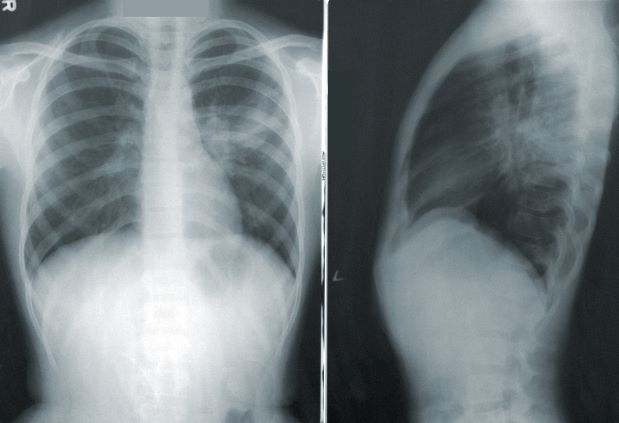

기본 검사 항목은

신체 계측, 시력 및 청력 검사, 혈액 및 소변 검사, 혈압 측정, 흥부 방사선, 구강 검진이 해당됩니다.